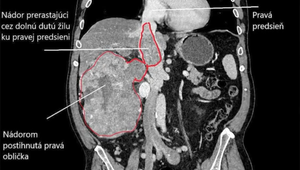

Zdroj: FNDR BB

Pacient na mimotelovom obehu